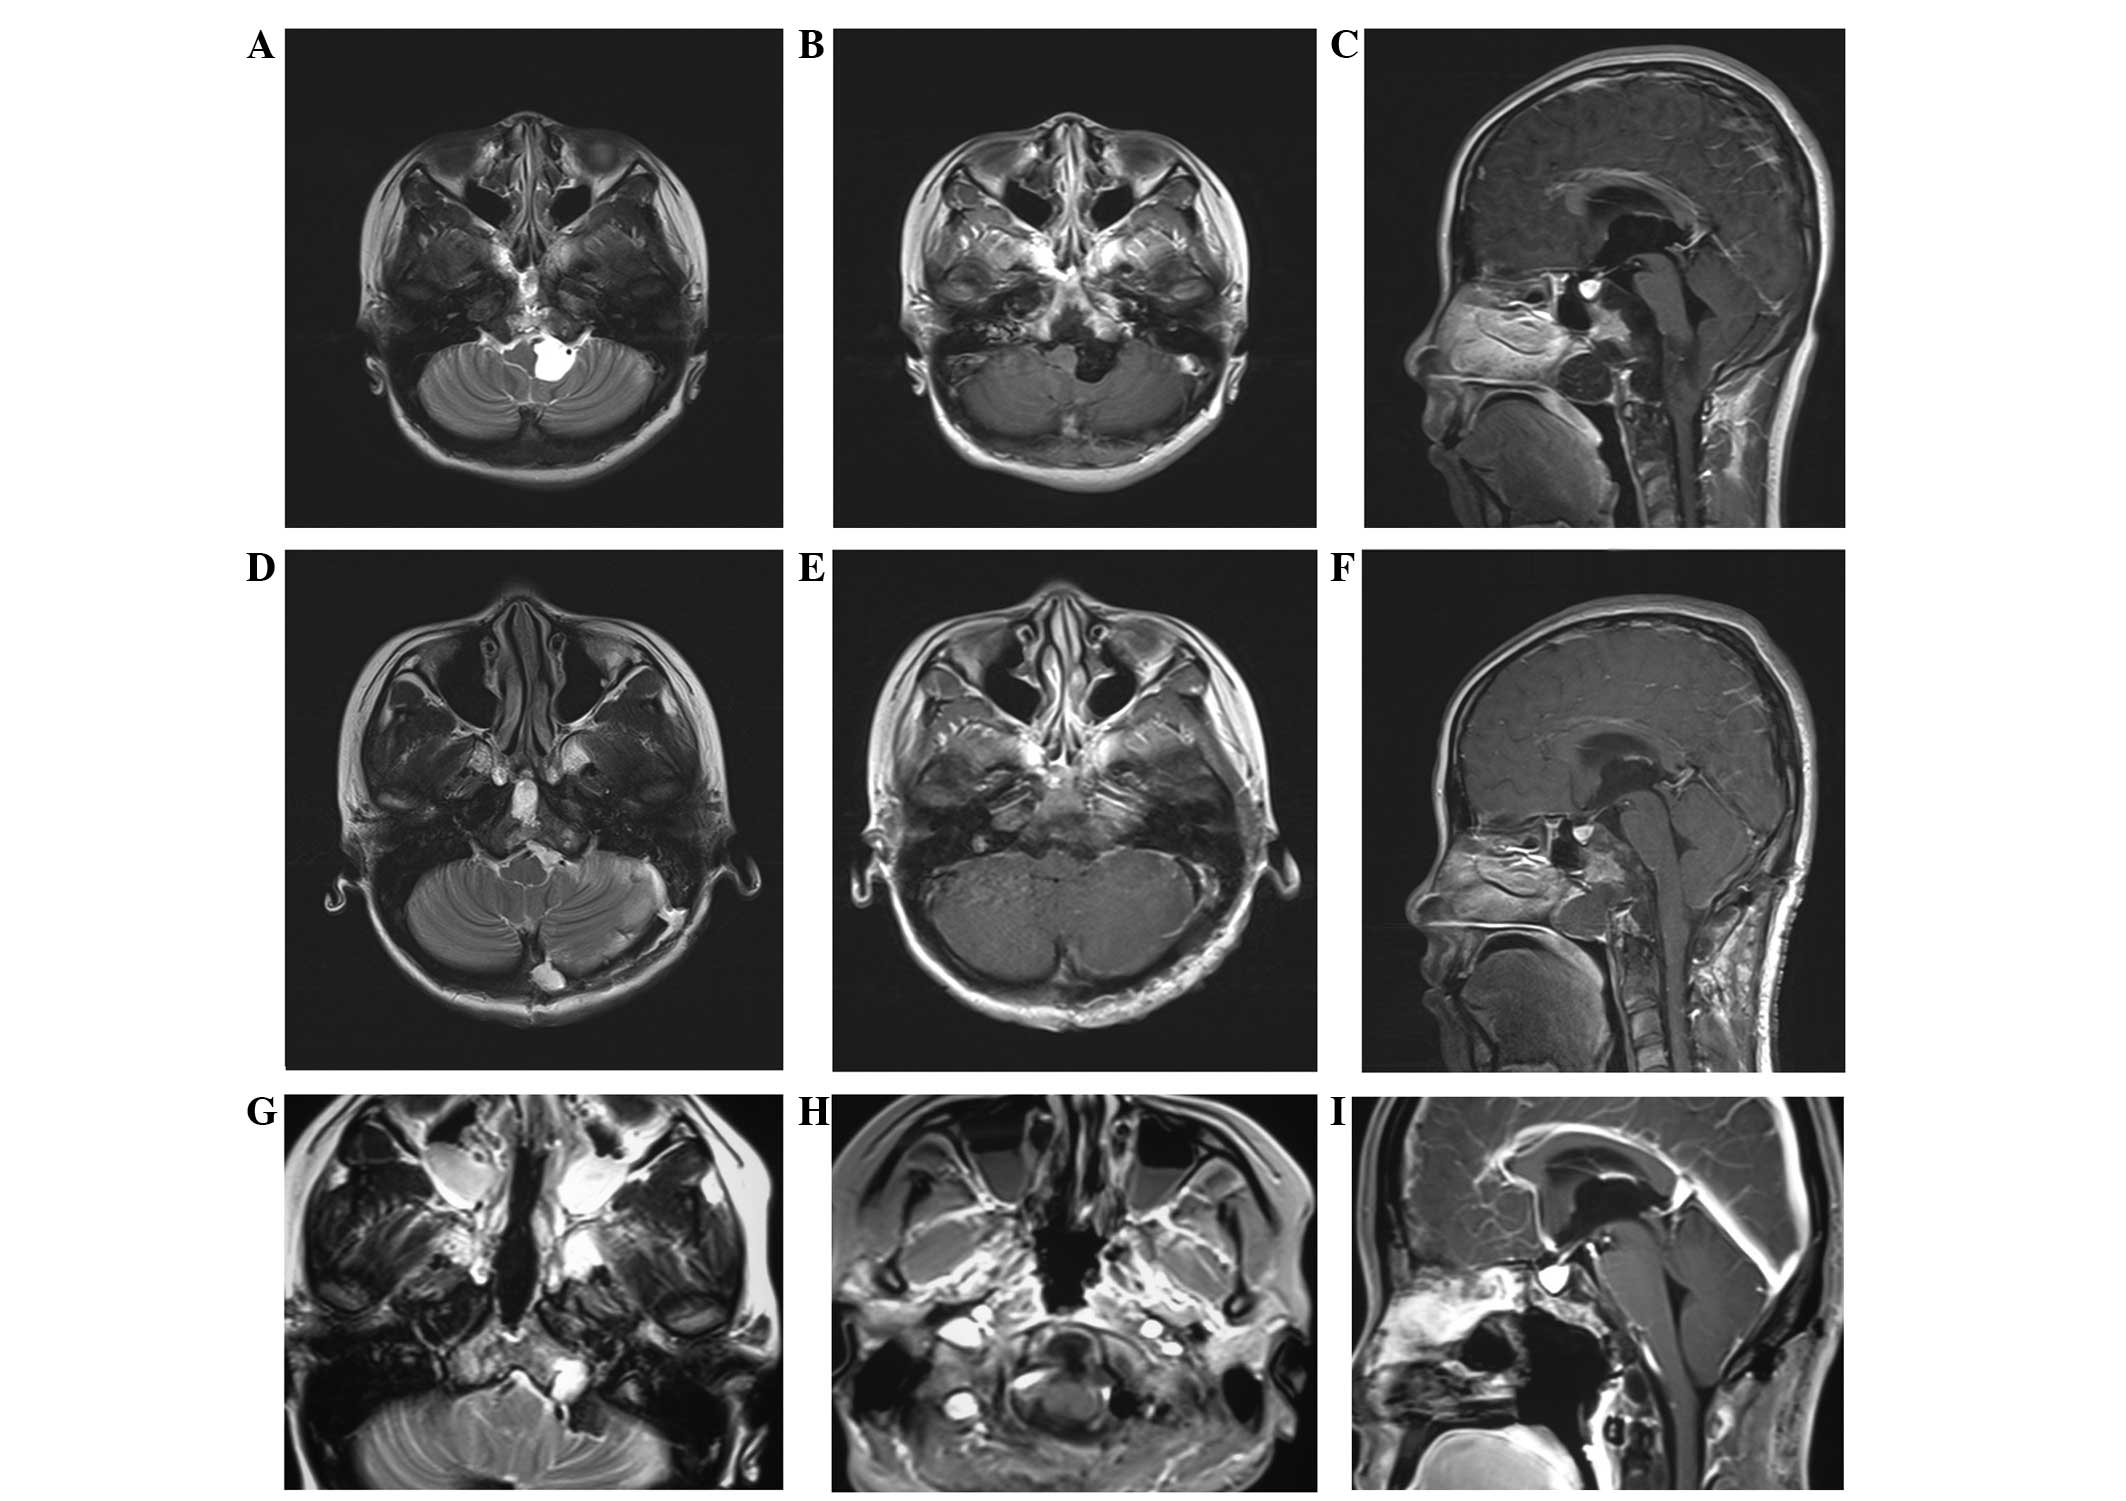

Supratentorial Tumors in the Pediatric Population ...

Supratentorial Tumors in the Pediatric Population ... from neupsykey.com